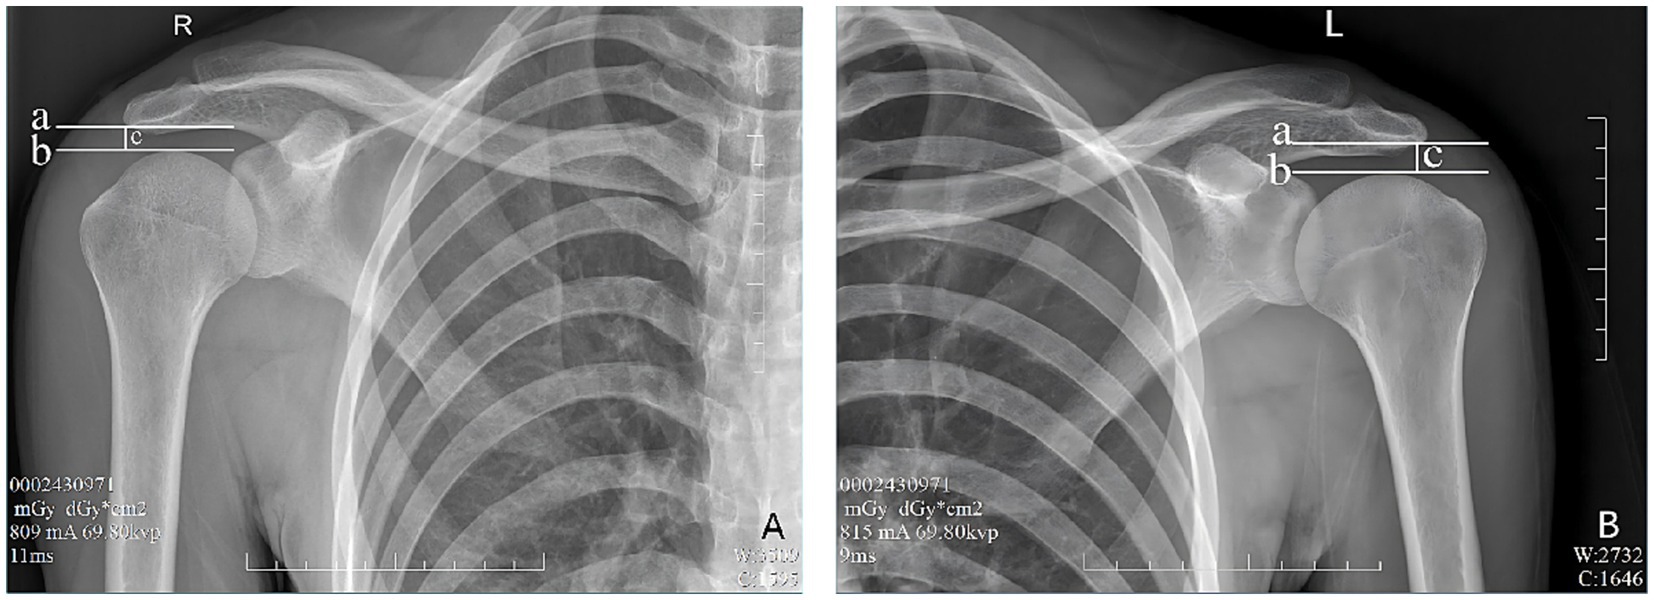

In the evaluation of AHD during radiographic procedures, the research included 28 healthy participants based on the informed consent of each participant. During the assessment via radiography (Simens Yiso, Fluorospot compact imaging systems, Germany) (Parameter settings: tube voltage 70 kV, automatic tube current, and small focal spot), participants were asked to maintain an upright position with their arms resting comfortably alongside their bodies and palms oriented towards their torso (Figures 1A,B). A vertical reference line was marked from the lowest point of the acromion, perpendicular to a horizontal line drawn from the top of the humeral head, which allowed for the measurement of the distance between the acromion and the humeral head (17) (Winning Health TView 6.1.0, Winning Health Technology Group Co., Ltd.) (Figures 2, 3). And the ratio of the bilateral distances was calculated (Left/Right). These procedures were performed by a single radiologist. It was made that the consistency of the results was evaluated for the distances from the healthy participant to the flat plane detector, measuring at 0 cm and 50 cm (Figures 1–3).

Figure 3

Evaluation of AHD distance from the healthy participant to the flat plane detector at 50 cm. a—A horizontal vertical line across the lowest point of the acromion. b—A horizontal line across the top of the humeral head. c—Distance between lines A and B, as well as AHD. (A) Right shoulder, (B) Left shoulder.